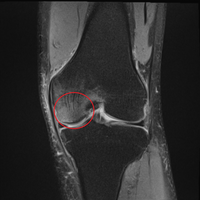

【膝の痛み】あれから1か月と少し。膝の話の続きです。

膝の痛みのその後の話です。 前回までの話はこちらです。 www.asaton.club www.asaton.club www.asaton.club 前回まででひどいお医者に嘘診察で高額の自由診療を勧められたり色々ありましたが、最終的には良いお医者様に出会えて、その後は定期的に運動療法を受けていました。 後は前々回書いた通り、食事にも気を付けて毎…